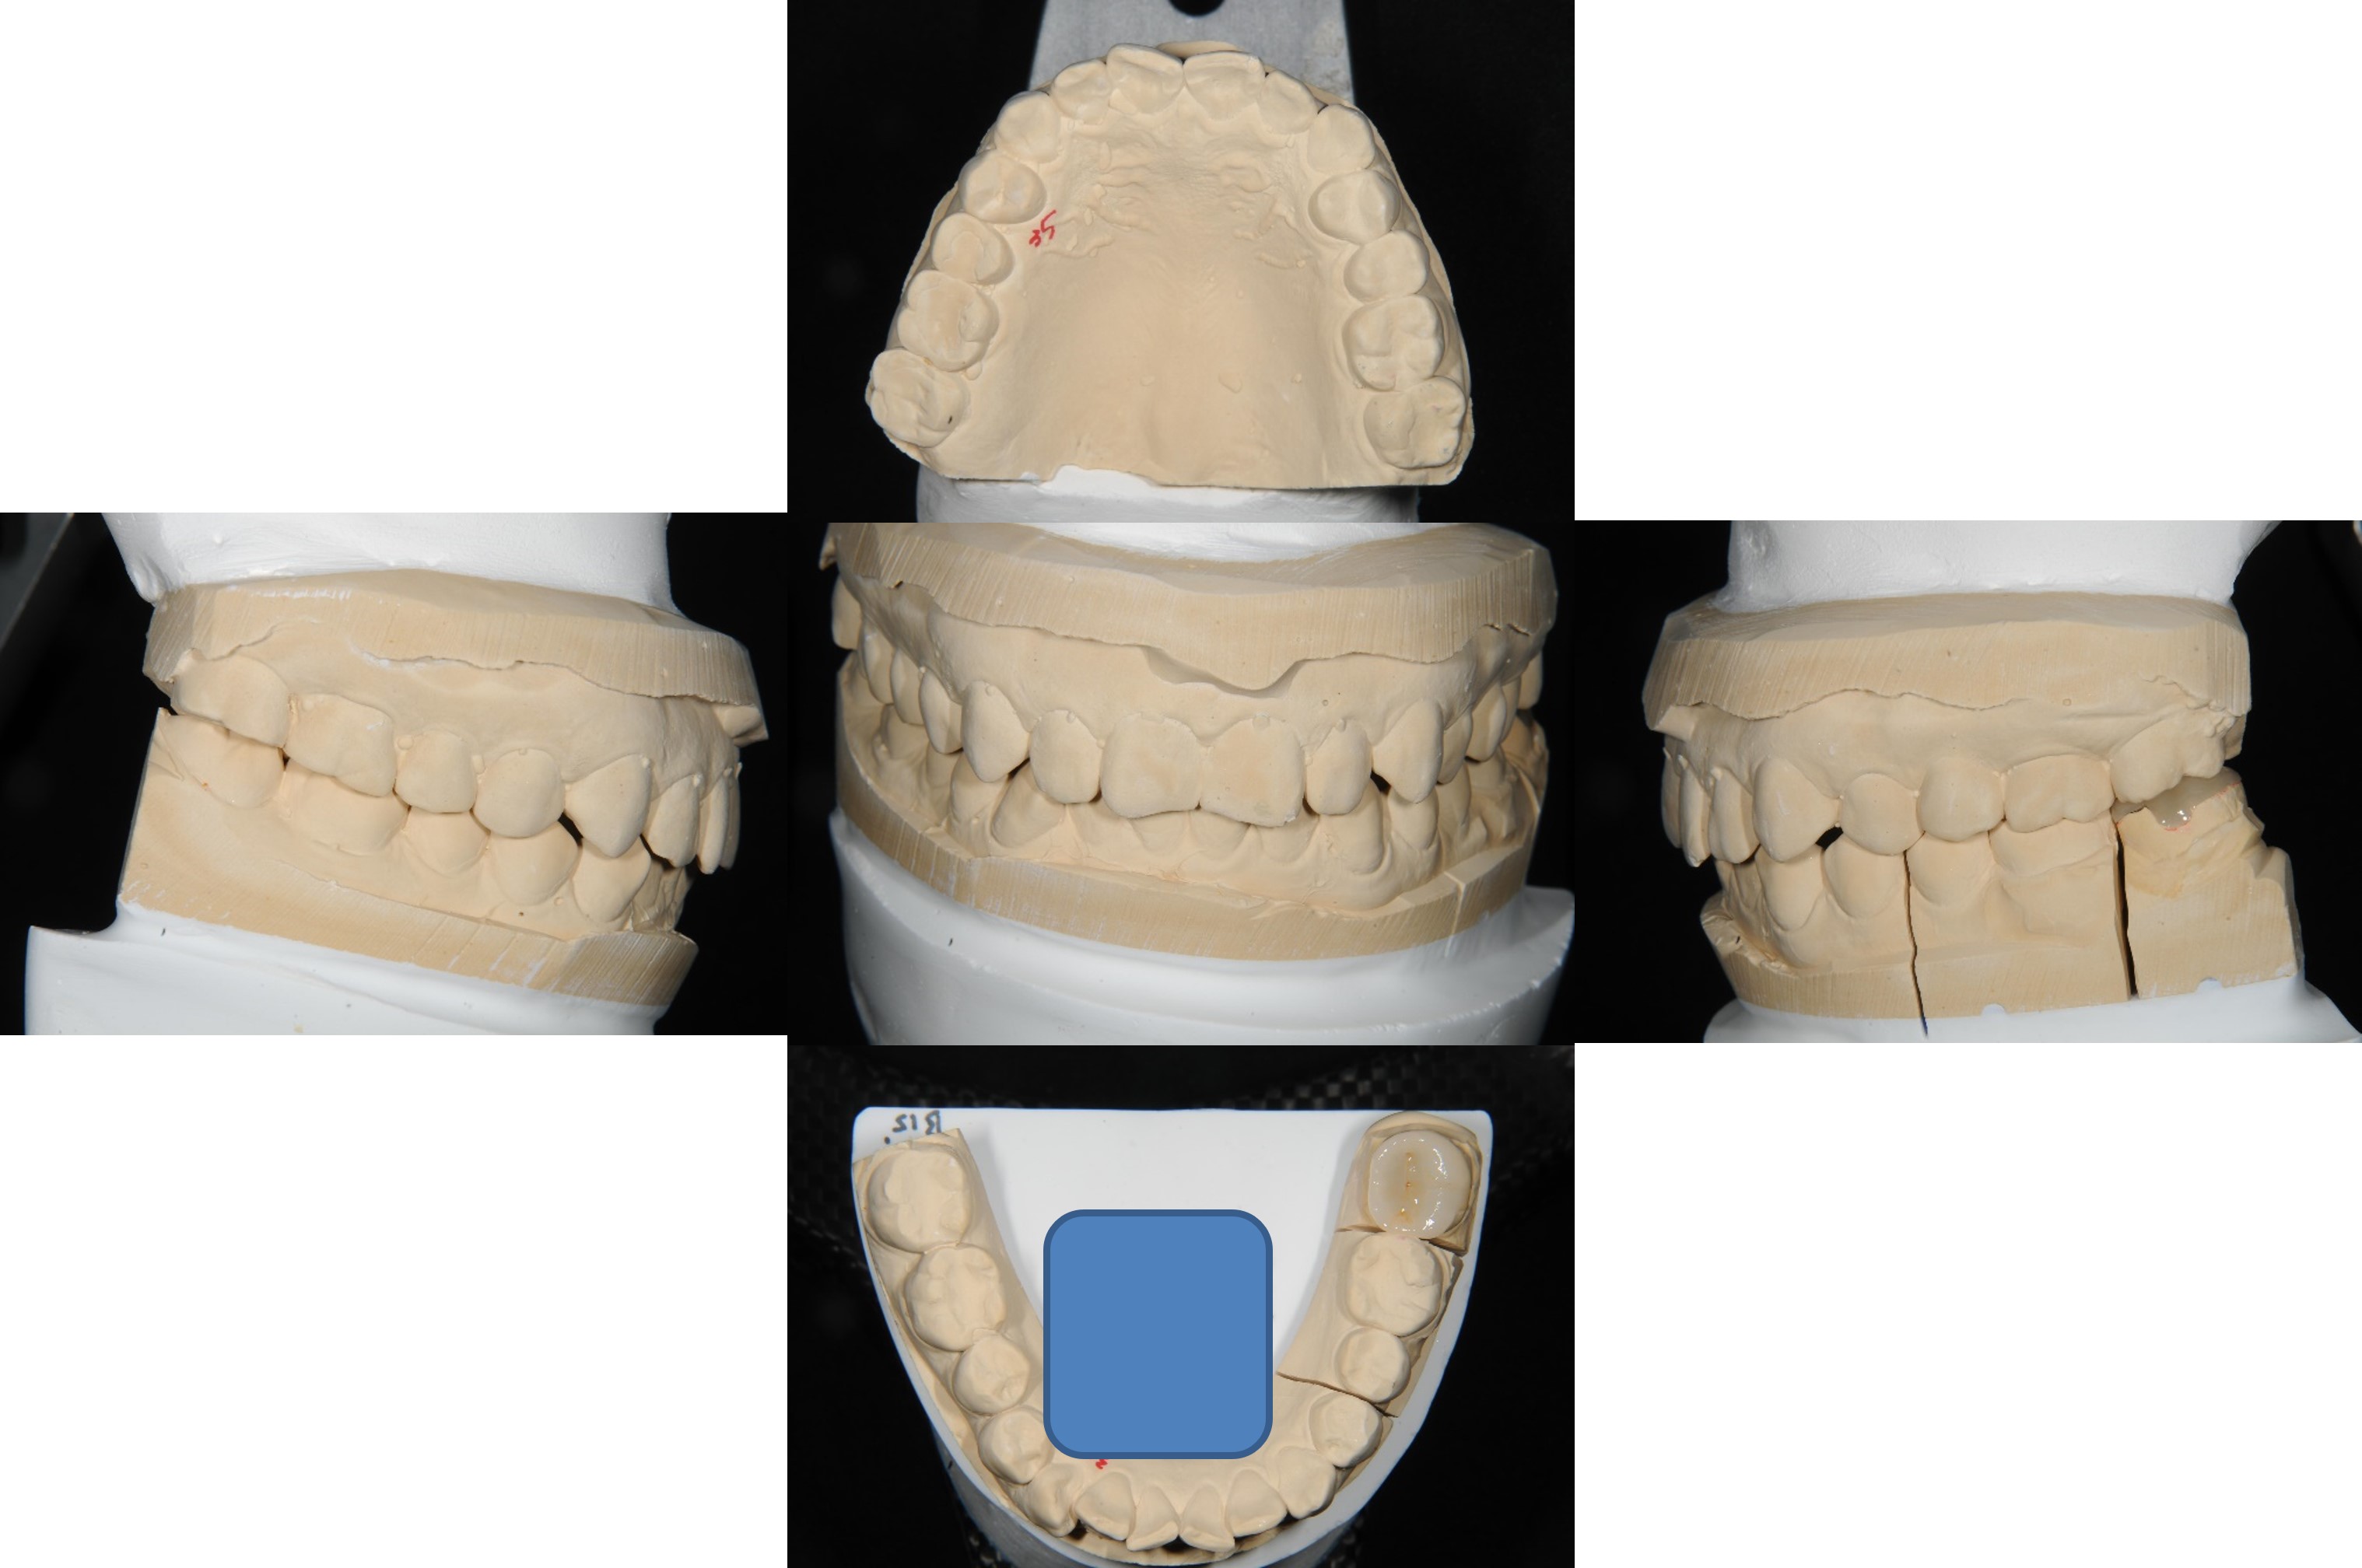

取面弓,上咬合器

陶瓷冠塊體製作